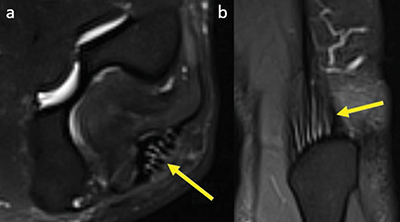

Figure 2

Axial (a) and coronal (b) fat-saturated T2-weighted image at the level of the triceps tendon insertion with a physiological linear T2-hyperintense signal compared to muscle parallel to tendon fibers, score 2.

Multiple linear T2-hyperintensities were seen distally in the triceps tendon parallel to its fibers among all patients (Figure 2). The common flexor tendon showed signal alterations in 8% of patients; 4% of them had an increased signal around the tendon (score 1) (Figures 3) and 4 % of the patients had an increased signal within the tendon (score 2) (Figure 4).

Pathology of the triceps [10] is rare, and it is extremely rare in the brachialis tendon [14]. Sevag et al. suggested that small linear signals are part of the normal tendinous structure of the triceps insertion [11]. These were present in our study too and are considered normal. No other signal abnormalities were noted in the triceps or brachialis insertion across all patients in this study, suggesting the pathology of these tendons to be extremely rare in presumable asymptomatic individuals too.